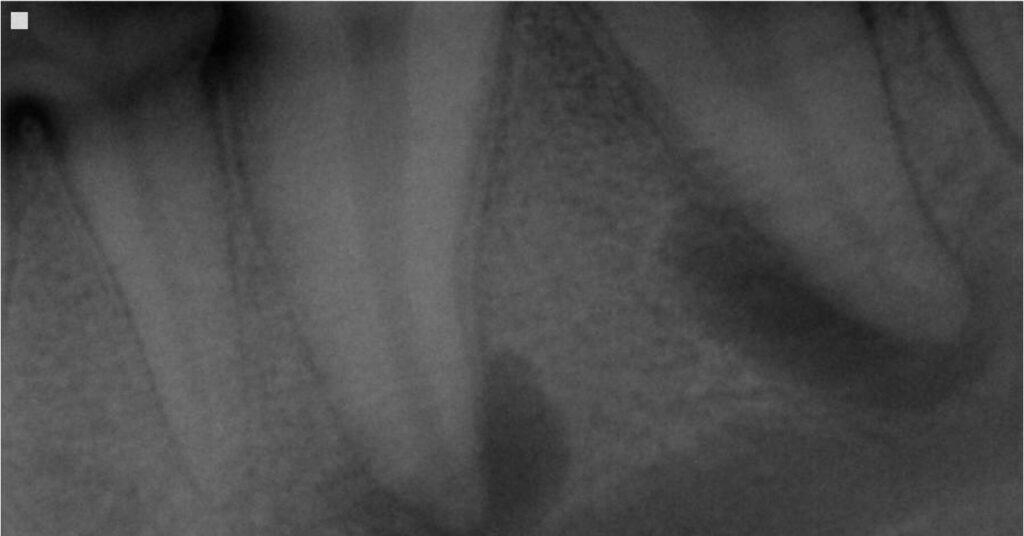

Dog Tooth Abscess: Is This an Emergency?

molar abscess radiograph

In general, a dog with a tooth abscess often requires urgent veterinary attention, but it is not usually life-threatening. We see many dogs arrive with facial swelling, hidden pain, or subtle behavior changes that trace back to an infected tooth. A tooth abscess forms when bacteria enter the inner structures of a tooth and create…